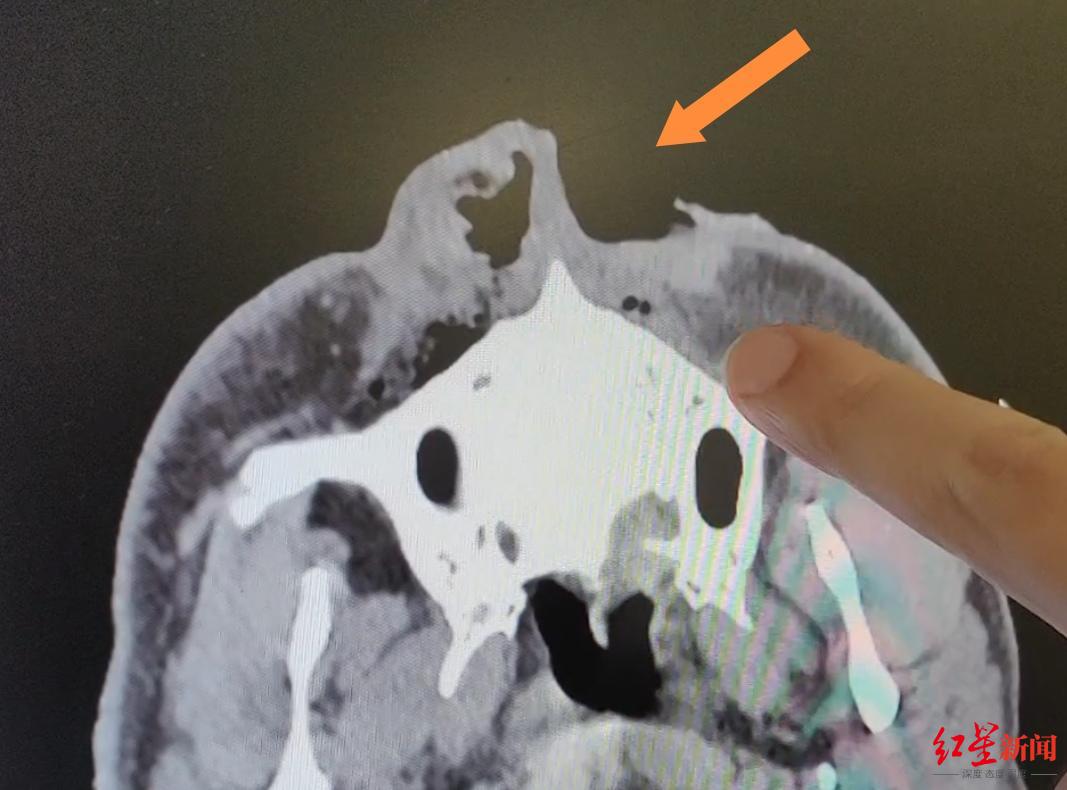

6月15日晚11时许,救护车将何云光送达四川省人民医院急诊科,整形外科医生崔玮收到急诊科的通知,紧急前往会诊。“他的伤势比较严重,整个脸都是血肉模糊的,身上到处都是抓伤、咬伤。”崔玮说:“不过,不幸中的万幸,他的生命体征平稳,CT检查发现没有伤及颅脑和内脏。”

何云光全身的裂伤,共约10处,其中最严重的,是黑熊的撕咬在他脸上留下的一道约15厘米长的伤口,让他眼皮、眼睑受损,泪小管断裂,失去一半鼻子。由于各处伤口污物较多,因此首先进行了精心的清创和连续两天的引流,确保他伤口内部的污物能够排出。